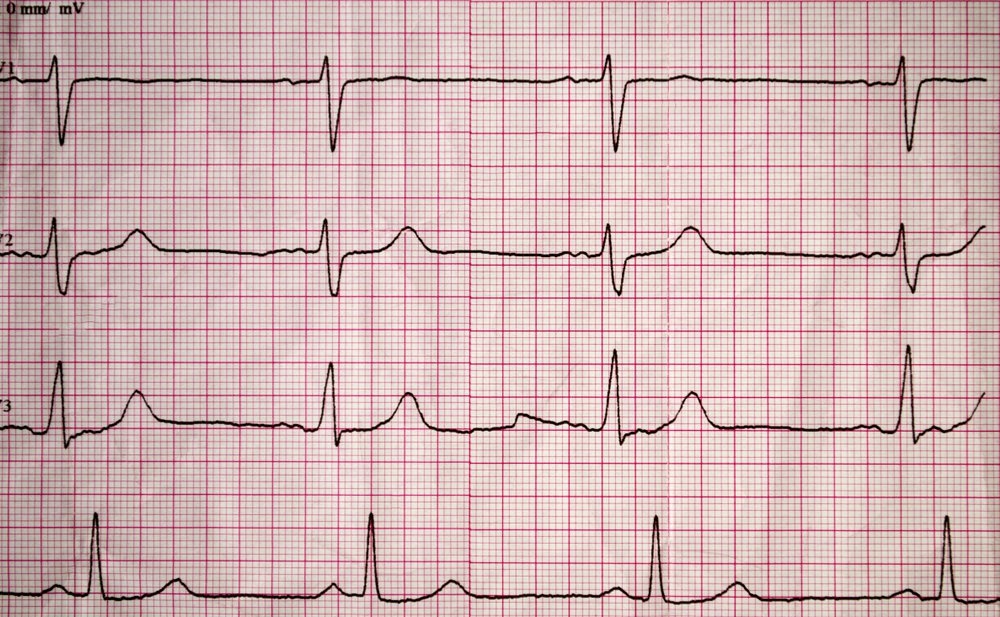

Bệnh tim: Bệnh động mạch vành và các vấn đề về tim mạch thường cản trở giấc ngủ. Trên thực tế, 44% người mắc bệnh tim gặp khó khăn với giấc ngủ. Nguyên nhân là vào ban ngày, chất lỏng tự nhiên làm sưng chân, sau đó, khi bạn nằm thẳng vào ban đêm, chất lỏng phân phối lại. Tuy nhiên, nếu trái tim không hoạt động tốt, những chất lỏng này có thể bị mắc kẹt ở tim và phổi. Lúc này, ngồi dậy sẽ giúp cơ thể phân phối chất lỏng tốt hơn, nhưng lại khiến bạn mất ngủ.